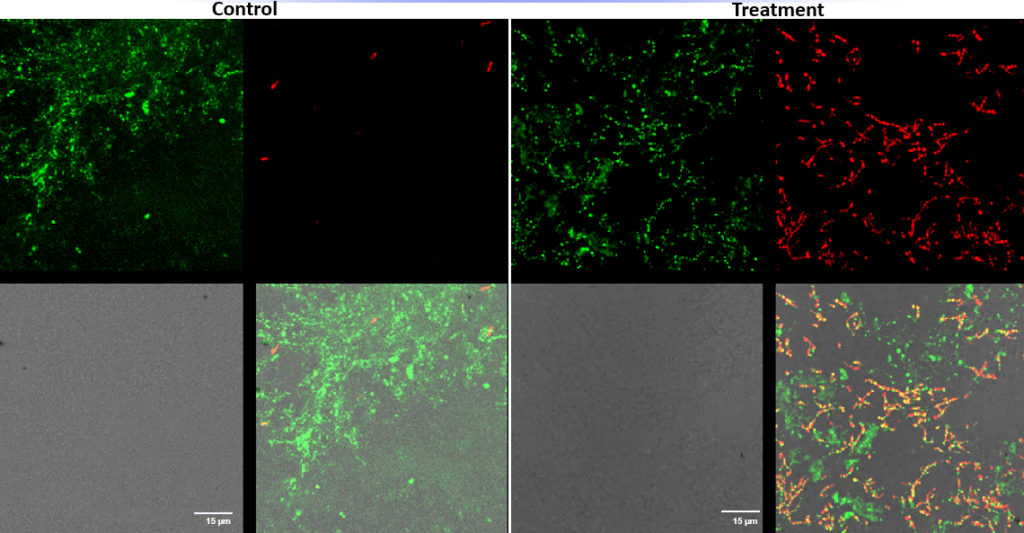

Pseudomonas aeruginosa – Superficial fluorescence microscopy. Microscopic imaging of Pseudomonas aeruginosa inoculated on the corneal surface and treated with UV-C for 15 seconds at a 10 mm distance. The images show clear bacterial membrane disruption and reduced viability, demonstrating the antimicrobial effectiveness of UV-C treatment on the superficial corneal layer.

Each image is divided into four quadrants: the upper left quadrant shows the green channel highlighting live bacteria; the upper right shows the red channel highlighting dead bacteria; the bottom right shows the merged green and red channels indicating live and dead bacteria; and the bottom left illustrates the bright field image. Bright green represents bacteria with intact membranes (live bacteria), red represents bacteria with compromised or dead membranes, and yellow represents bacteria with partially compromised membranes. Scale bar: 15 µm.